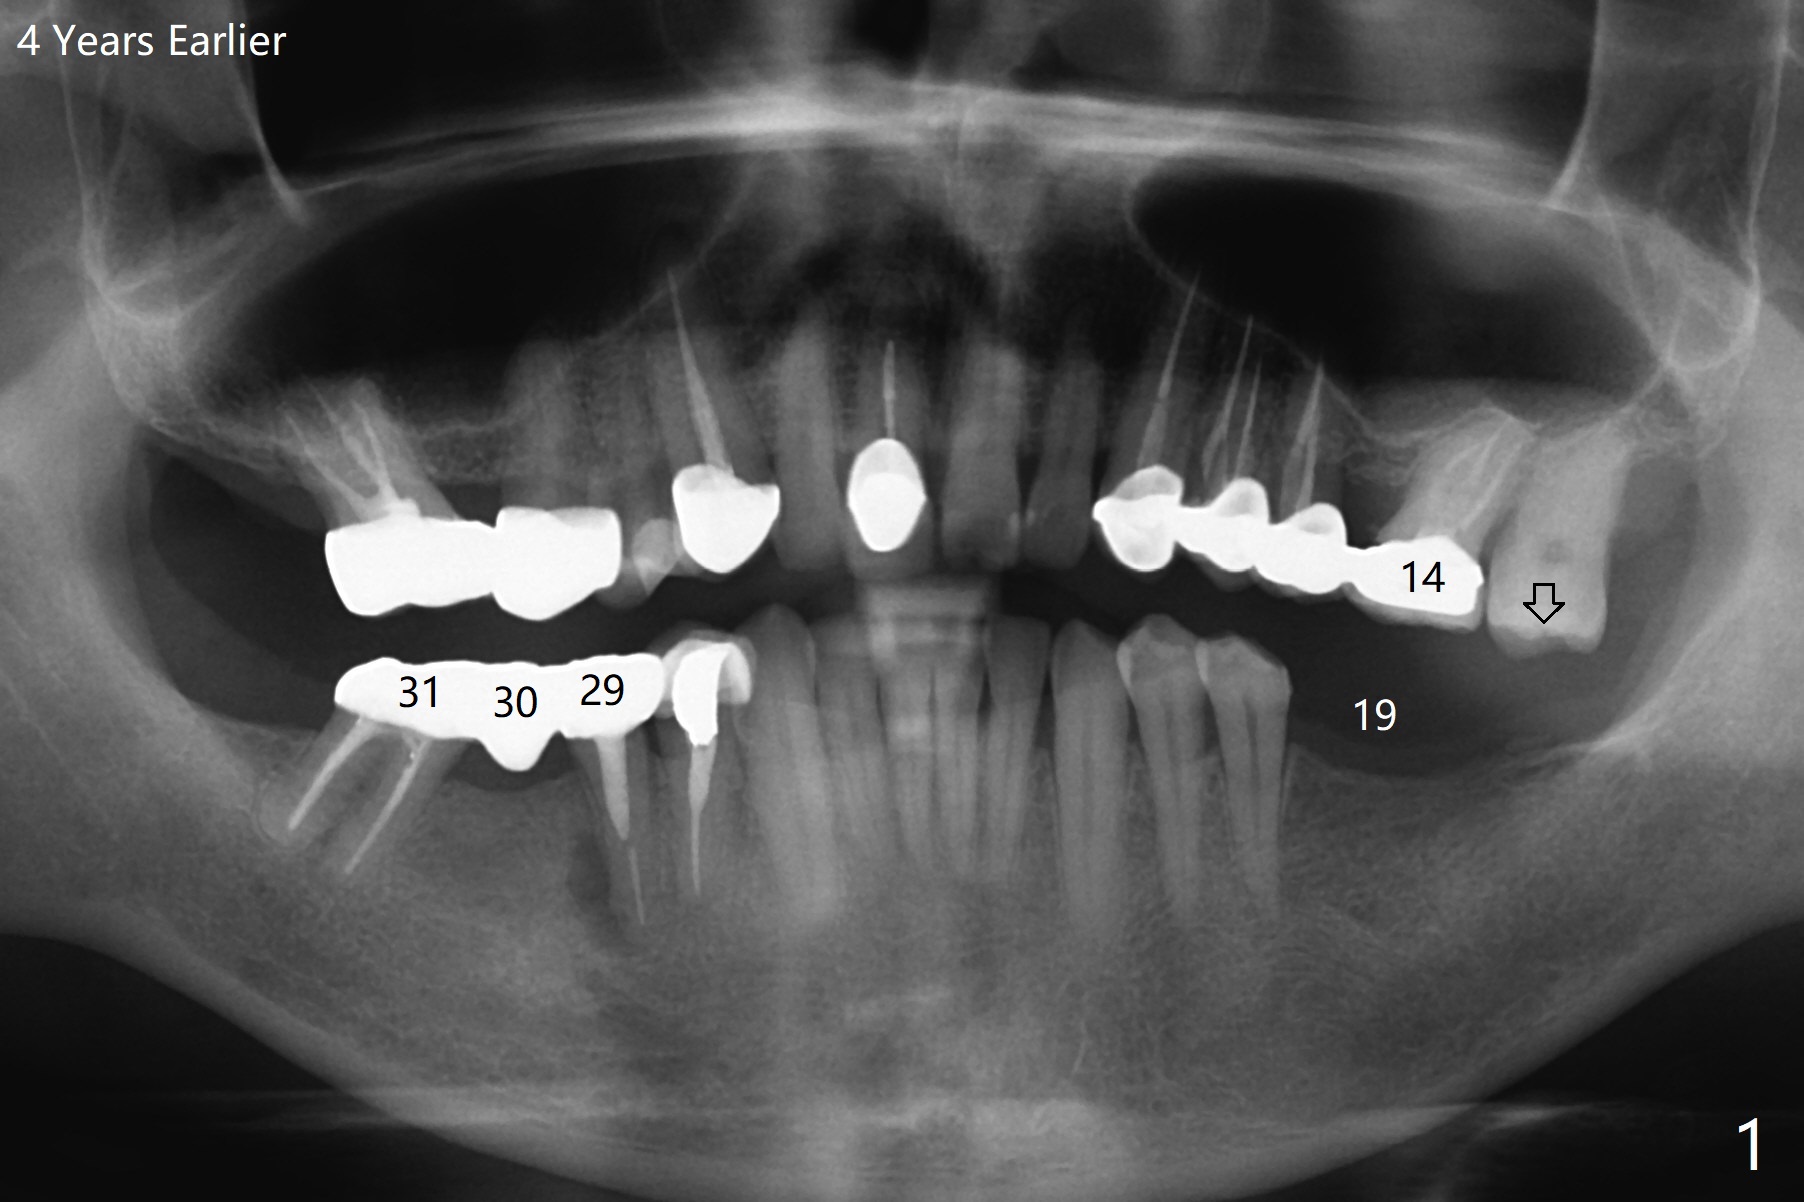

A 55-year-old man agrees to have implant(s) to be placed on the left side 4 years post #29 and 30 implantation. Recently the tooth #31 lost crown (Fig.1). Since the tooth #15 is supraerupted, an implant will be placed at #19 first. A 4 mm implant will be placed in the narrow ridge of #19 (Fig.2).